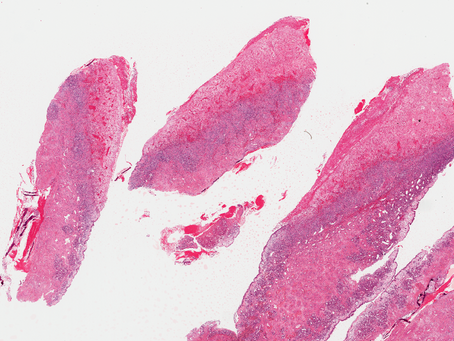

GYN Case 1. Endometrial curretage from a 40 year old patient.

•Diagnosis: epithelioid trophoblastic tumor (ETT) •ETT is a malignant neoplasm of chorionic-type intermediate trophoblast •The rarest of...